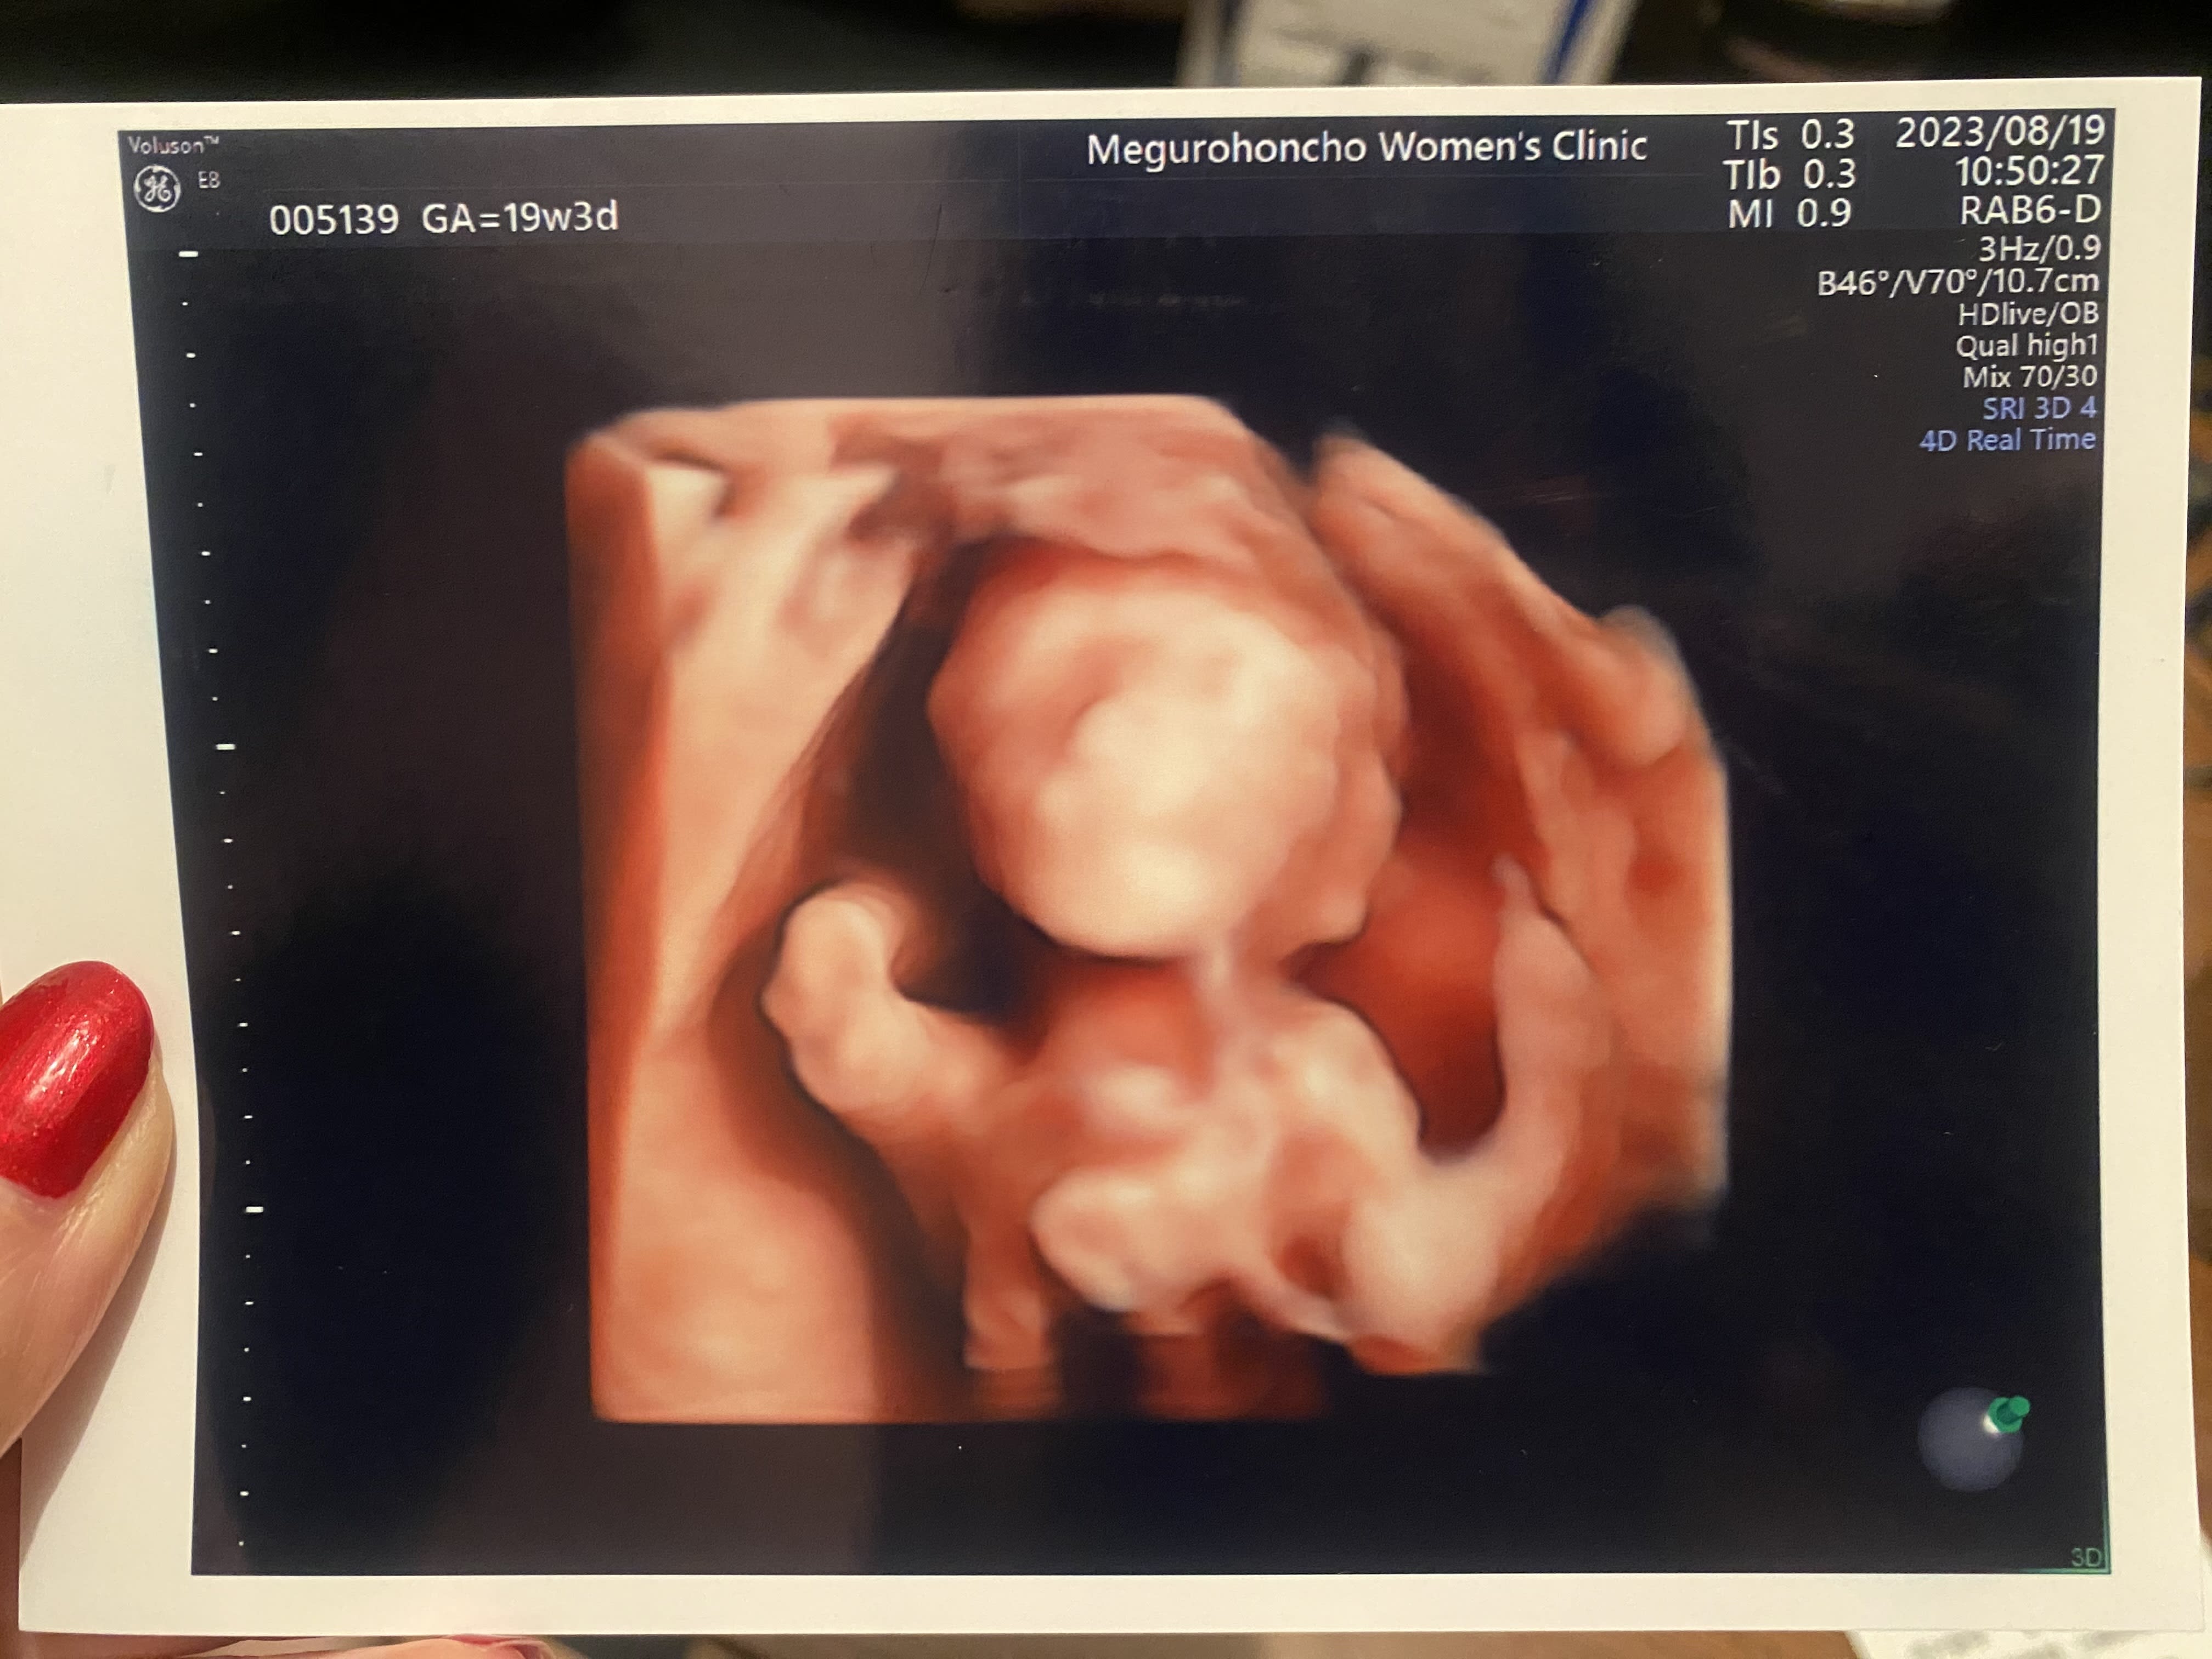

19週 初めて4Dエコーで顔が見れるようになった! まだ鮮明じゃなくてわからないけど、小さい耳や鼻が少しずつわかるようになった。 次の日に神社に安産祈願にいったよ。元気に生まれてきてくれますように😊

18 Aug 2023